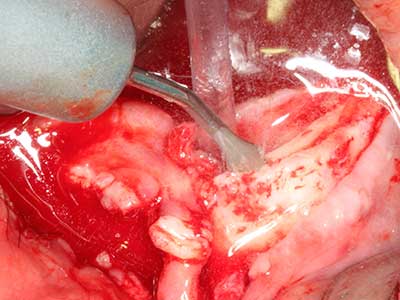

When surgical procedures are performed on bone in the immediate vicinity of sensitive structures such as blood vessels or nerves, rotary instruments pose a significant risk of iatrogenic injury. Piezoelectric devices can be helpful for preparation of bone covers and removal of hard tissue close to nerves, particularly for exposure of nerves after iatrogenic injury but also during nerve lateralization for resective and reconstructive procedures or implant placement (Fig. 17-20). Light contact between the piezotip and the nerve does not generally result in damage but proceeding incautiously with saw-like motions or attachments where a residual bone substrate remains may cause temporary or even permanent nerve damage. However, the risk of damage is considered to be substantially lower than when using saws or milling instruments (Pereira, Gealh et al. 2014).